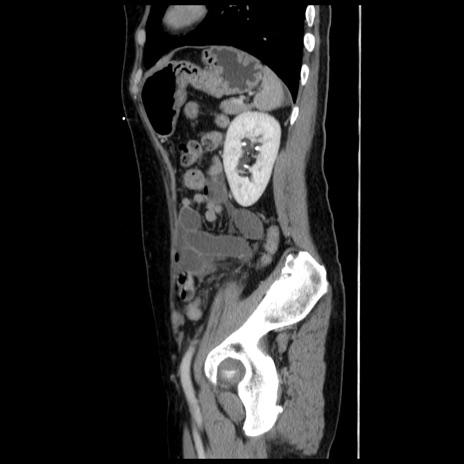

症例10(矢状断像)

【症例】 50歳代女性

【主訴】 腹痛

【現病歴】前日生レバーを食べた。今朝に排便あり。 昼前に突然発症の腹痛を生じ、当院救急外来を受診した。

【既往歴】 子宮筋腫にてで子宮全摘後

【身体所見】 意識清明、腹部:平坦、軟、下腹部やや左を中心に圧痛・反跳痛あり、筋性防御あり

【データ】WBC 7800、CRP 0.07